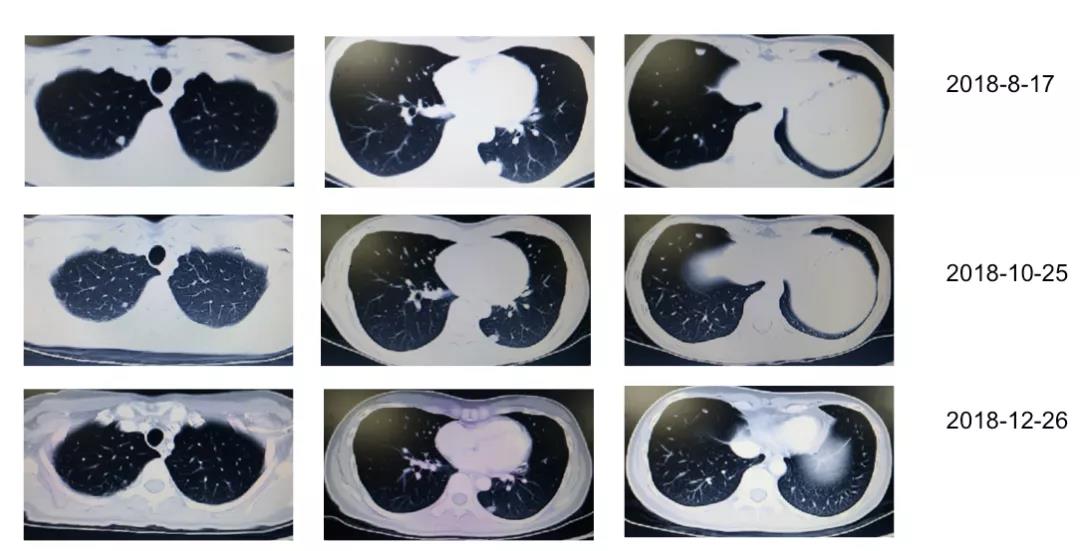

2018年8月17日复查胸腹CT示术区未见占位;腹膜后多发淋巴结肿大,考虑转移。双肺多发结节影,考虑转移瘤可能(图2)。肝S4段结节影,不典型血管瘤,与转移瘤鉴别。CEA 128.6 ng/ml。2018年8月至12月行“贝伐珠单抗+FOLFIRI”方案化疗8周期,具体用药为伊立替康230mg d1,CF 0.5 d1,5-Fu 0.5 iv d1、5-Fu 3.0 CIV46h +贝伐珠单抗200mg d1;q2w。期间复查胸腹CT:双肺多发转移瘤缩小(图3)。CEA持续下降。

3月后疾病再进展,呋喹替尼显疗效